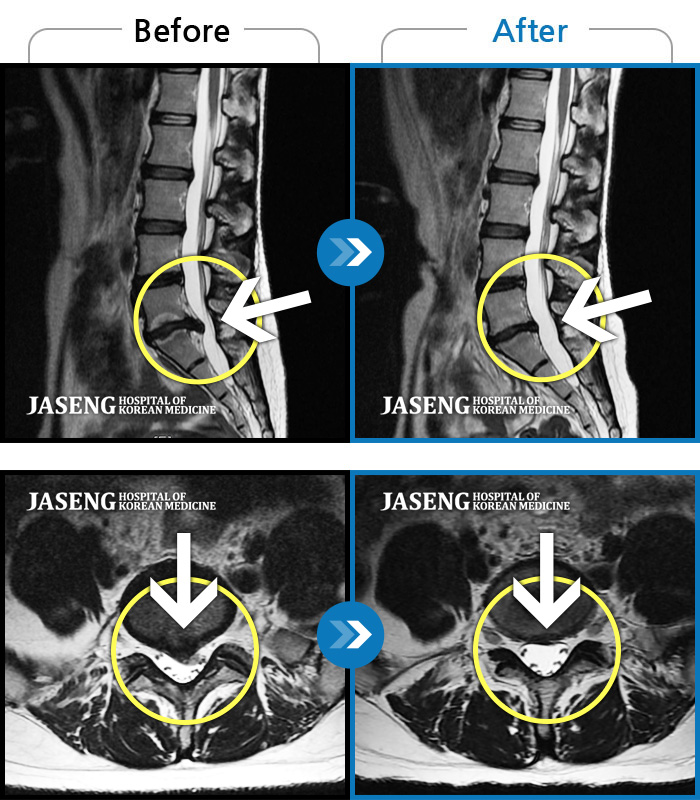

영상결과만보면 너무심각하다고 하셨지만

한번 할수있는데까지 해보자면서 지금까지오고 있습니다

항상 웃으시며 치료나 상태에대해 이야기해주시는 원장님을 좋은결과가있길 소원하며 칭찬합니다^^